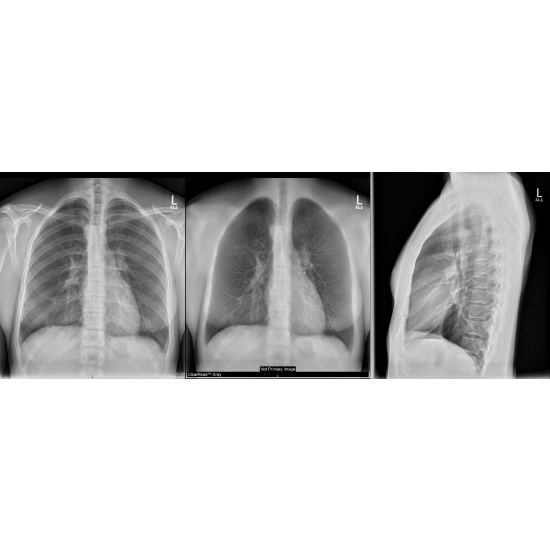

CT angiogram chest: Mild tracheal narrowing associated with a vascular ring and a right aortic arch Case Photo #2 Case Photo #3 .